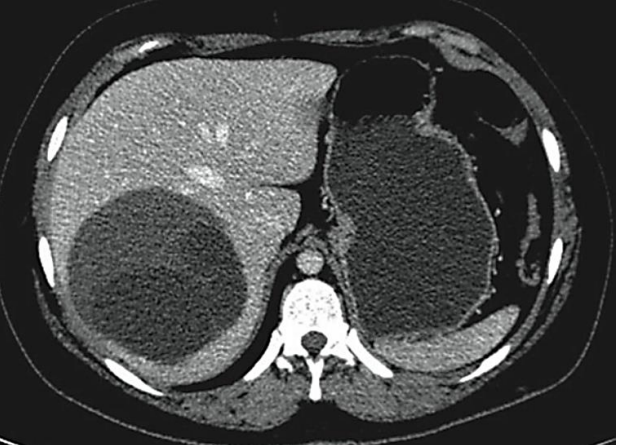

Analise a imagem a seguir.

Assinale a alternativa que apresenta qual hipótese diagnóstica está relacionada ao achado da imagem.